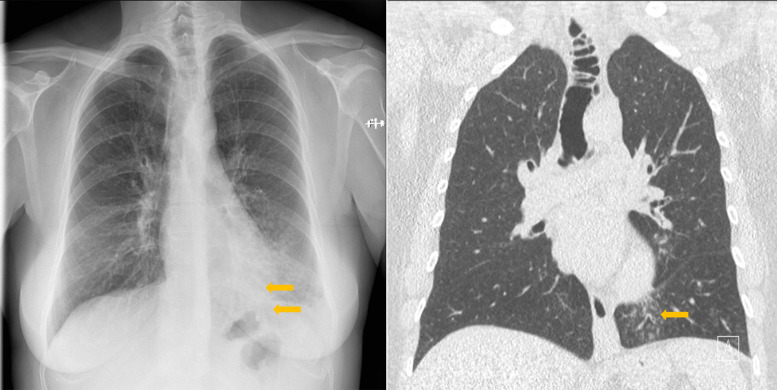

教学要点气管憩室病是一种罕见的良性疾病,其特征是单个或多个气管壁外袋,可以是先天性的,也可以是后天性的,通常在胸部高分辨率计算机断层扫描中偶然被诊断出来,一般情况下没有任何症状。

Teaching point: Tracheal diverticulosis is a rare and benign disorder, characterized by single or multiple tracheal wall outpouchings, either congenital or acquired, usually diagnosed incidentally on chest high‑resolution computed tomography, and in general remaining asymptomatic.